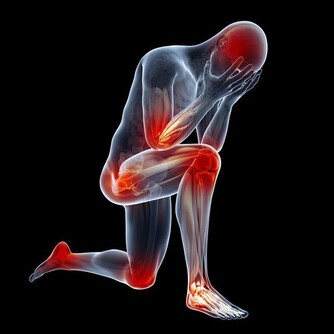

腎虛是由於腎不能固精,導致腎精嚴重流失,體內的腎精就會匱乏。如果自身患有腎虛,我們就會出現臉色蒼白、喘息以及頭髮還會出現嚴重脫落等症狀表現,如果腎虛更嚴重的話,甚至還會導致男性不育等情況。腎虧的症狀主要表現為腰膝酸軟、乏力、心煩易怒以及眩暈耳鳴等。